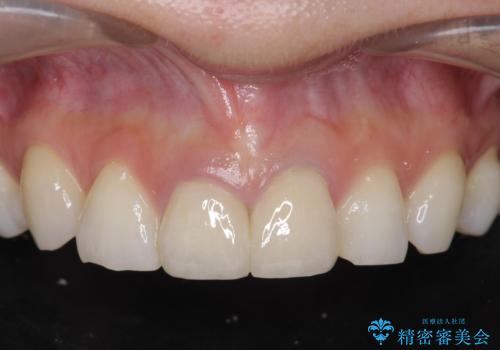

[ 前歯セラミック治療 ]白く不自然な前歯をきれいにしたい

![[ 前歯セラミック治療 ]白く不自然な前歯をきれいにしたいの症例 治療前](https://seimitsushinbi.jp/wp/wp-content/uploads/2021/12/bece58cb17cb8130ee0502c0be252341-500x350.jpg?v=1640157784)

![[ 前歯セラミック治療 ]白く不自然な前歯をきれいにしたいの症例 治療後](https://seimitsushinbi.jp/wp/wp-content/uploads/2021/12/e6beb0177fa3816df180668db670061d-500x350.jpg?v=1640157796)